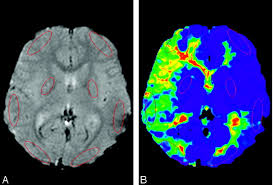

모야모야병은 뇌 기저부에 있는 주요 혈관이 점차 좁아지면서 뇌로 가는 혈류량이 줄어드는 질환입니다. 혈류가 부족해지면 뇌는 새로 가늘고 약한 혈관을 만들어 혈류를 보완하려고 하는데, 이 혈관들이 모여 있는 모습이 연기처럼 보여 ‘모야모야’라는 이름이 붙었습니다.

모야모야병은 뇌혈류가 급격히 바뀌는 상황에서 증상이 쉽게 유발됩니다.